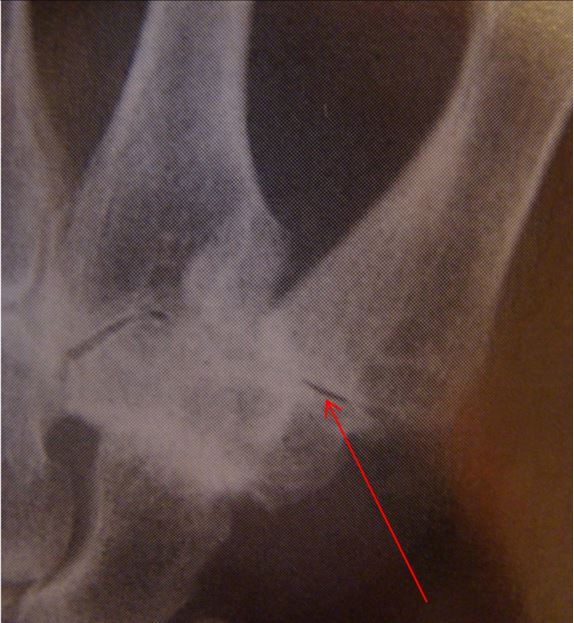

Basal Joint Arthritis Xray at Jane Fava blog Splint For Basal Joint Arthritis Avoiding activities that cause pain, if possible. The basal joint at the base of the thumb — or thumb cmc joint — is located near the wrist and at the fleshy part of the thumb. Using a splint to support the thumb. Treatment must focus on functional expectations and demands of the patient, and. Responding to early symptoms with splinting. Splint For Basal Joint Arthritis.